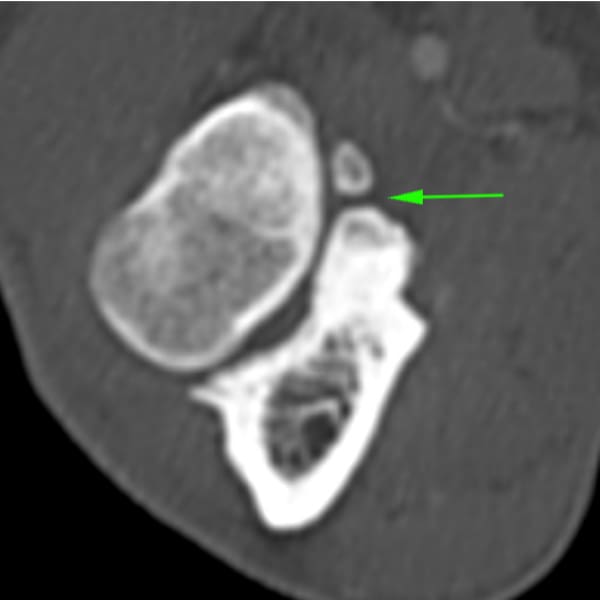

La Tomografía computerizada (CT) o TAC es la técnica por imagen de elección. El procesado avanzado de la imagen nos permitirá visualizar finos cortes de la anatomía y detectar pequeñas lesiones (por ejemplo, fragmentación del proceso coronoides), las cuales son difíciles de diagnosticar en radiografías convencionales.

• Enfermedad del proceso coronoides medial (EPCM): se trata de la condición más encontrada de todas las que se incluyen en la displasia de codo. El proceso coronoides puede encontrarse malformado, fisurado e incluso fragmentado. Como resultado de esta enfermedad y del roce anormal de dicha estructura con la superficie articular del cóndilo humeral medial, se produce un desgaste acelerado de las superficies cartilaginosas del aspecto medial del codo dando lugar al Síndrome del compartimento medial, el cual se ve favorecido por la sobrecarga que soporta la región interna de la articulación en condiciones fisiológicas.